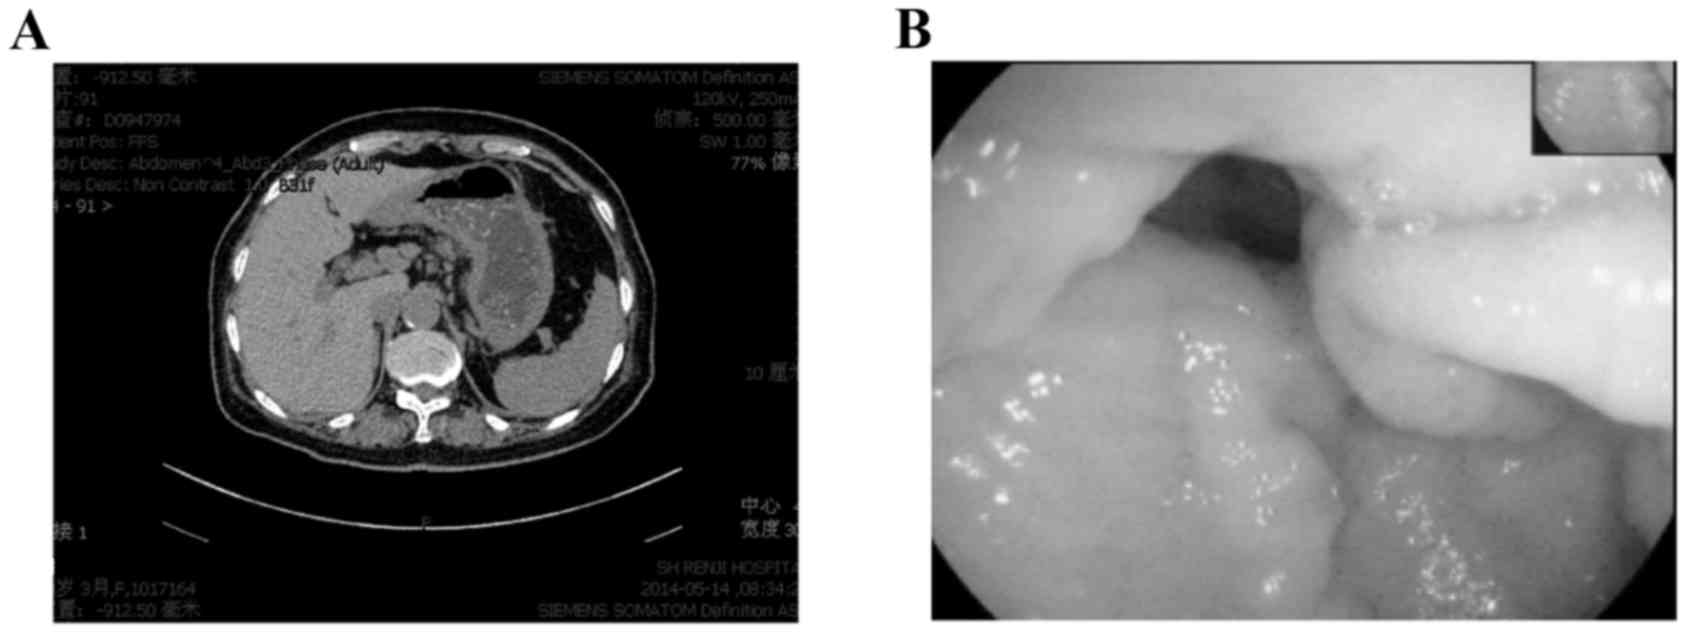

Radiographic And Endoscopic Regression Of Metastatic Gastric Cancer To The Colon In The Setting Of 5 Aminosalicylic Acid Use Patel Journal Of Gastrointestinal Oncology